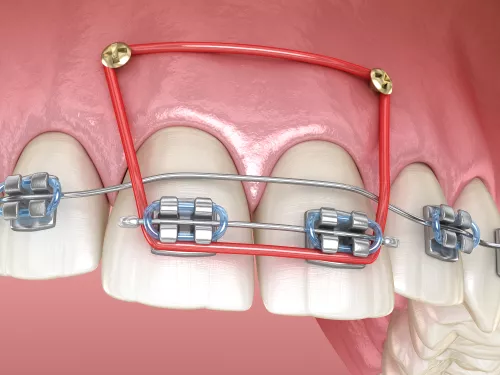

שימוש בכפתורים וגומיות בין לסתיות

לעיתים במהלך הטיפול ישנו צורך בסגירת מנשך פתוח שנובע מעמדה לקויה של הלסתות ו/או השיניים ואינו מאפשר מגע בין השיניים העליונות לשיניים התחתונות, לצורך זה יש לעיתים להרכיב גומיות בין לסתיות שלרוב מעוגנות בכפתורים מהסוג המודגם בתמונות.

גומיות בין לסתיות

לקראת סוף הטיפול בחלק מהמקרים יהיה צורך בגומיות שהמטופל מרכיב מלסת אחת לשניה. הן קלות להרכבה עצמית, ומאפשרות לרופא לסיים את ישור השיניים עם סגר תקין וסידור שיניים נכון. את הגומיות יש להרכיב לפי הוראות הרופא למרבית שעות היום.